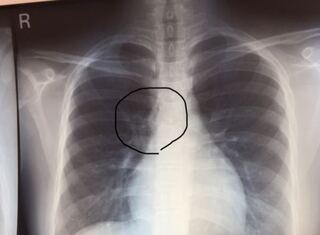

日々の症例 87 奇静脈葉間裂 Azygos Fissure

奇静脈葉とは X線 Ct画像診断のポイント Azygos Lobe

なまけもの家庭医の日記 奇静脈葉間裂

奇静脈葉 Azygos Lobe 一端の画像診断医を目指して

正常像 正常変異 Mediflex Incorporated